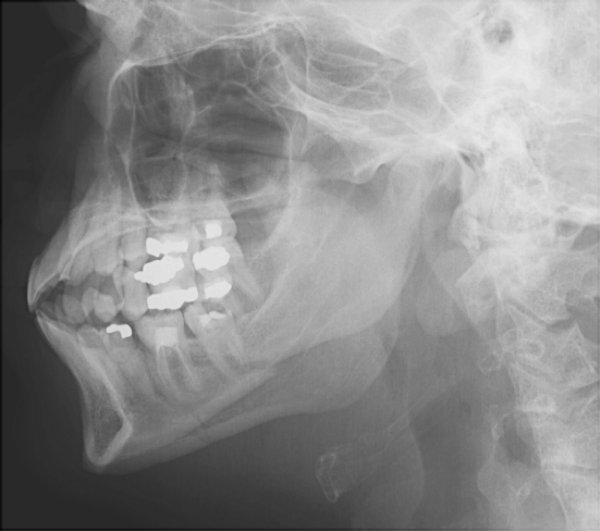

Return to Mandible Fracture